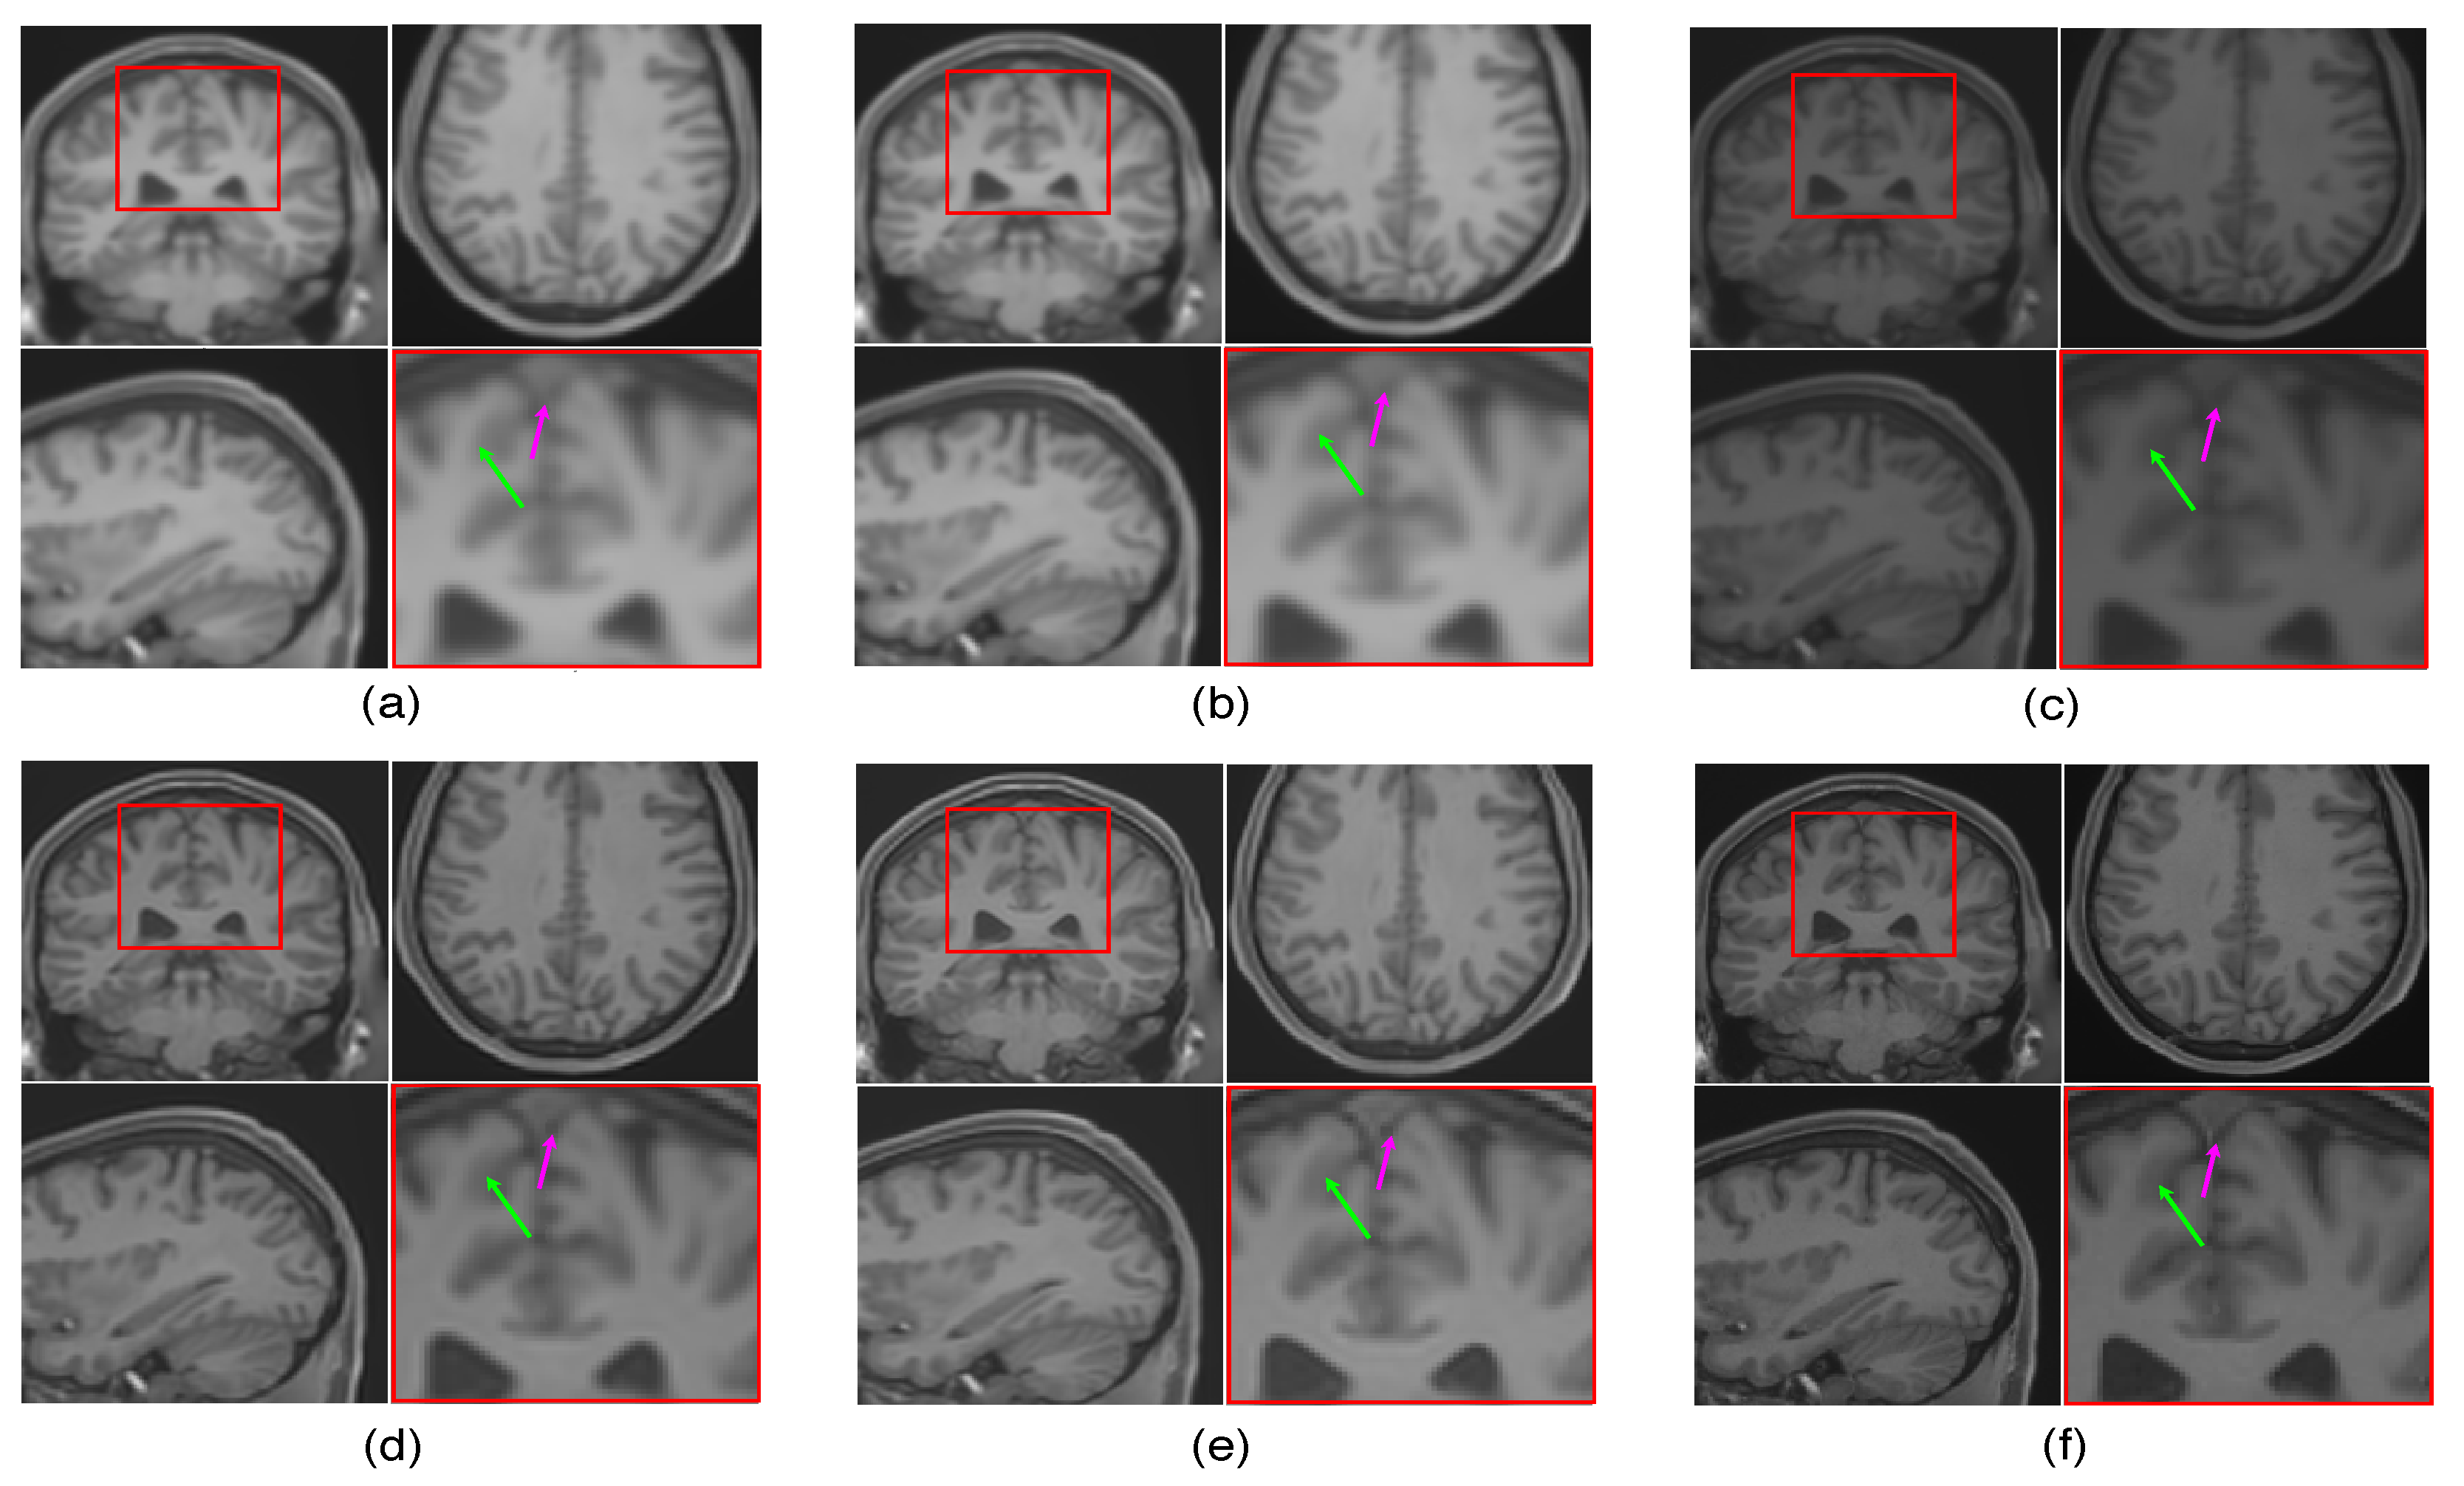

The LR image volumes are simulated by blurring the HR image volumes using a Gaussian kernel of the standard deviation of one voxel size and followed by downsampling. One MR image volume is randomly selected from dataset-II and super-resolved with super-resolution factor (SRF) 2 using the proposed SR approach and is compared with the existing state-of-the-art unsupervised methods NLM3D [13] and LRTV [12]. The reconstructed images using these approaches are shown in Figure 9. The highlighted region in the coronal slice is zoomed and shown in the red box. The pink and green arrows show the location for tissue boundary between cerebrospinal fluid (CSF) and gray matter, and white matter and gray matter, respectively. It can be observed that the proposed approach reconstructs the image details with relatively sharper tissue boundaries as well as better preservation of image details (near green arrow) as compared to the existing methods. Table 2 shows the mean PSNR, SSIM and FSIM values computed for different subjects for SRFs 2 and 3 reconstructed by different methods. The graphical representation of Table 2 is shown in Figure 10. It can be observed that the proposed approach provides comparably higher PSNR, SSIM, and FSIM values than existing methods, and thus illustrates the advantages of the proposed work in pixel-intensity, and structural and gradient-feature-based similarities, respectively.

Figure 9.

Illustration of reconstruction results for real MR image volume for super-resolution factor 2 using different super-resolution algorithms: (a) nearest neighbor interpolation, (b) spline interpolation, (c) non-local means [13], (d) low rank and total variation (LRTV) [12], (e) the proposed method, and (f) the original denoised high resolution (HR) image. Zoomed version of the red box shown in the axial slice is shown to demonstrate the difference (specifically in tissue boundaries indicated with arrows).

To emphasize the significance of reconstruction of uncommon image details in the proposed SR method, we chose a real MR image volume with a cavernoma and improved its resolution by factor 2, as shown in Figure 11. It can be observed that the LRTV [12] approach in Figure 11d reduces the blur as compared to interpolation and NLM3D [13] in Figure 11b,c, but tends to produce staircase effect. It can be observed that the tissue boundaries and image details inside the cavernoma, shown in the red box, are more clear and distinct for the proposed method. In addition, the skull outlines can be seen to be well defined (in the sagittal plane) in the case of the proposed algorithm (see Figure 11e) as compared to existing methods.

Figure 11.

Illustration of super resolution results for structural deformity cavernoma in real MR images, by different algorithms: (a) nearest neighbor, (b) spline interpolation, (c) non local means in three dimensions (NLM3D) [13], (d) low rank total variation based method (LRTV) [12], (e) the proposed approach, and (f) the original HR image. Each slice in axial, sagittal, and coronal planes is shown. The zoomed version of the cavernoma region from the coronal slice is highlighted in red rectangle. Please zoom for better visualization.